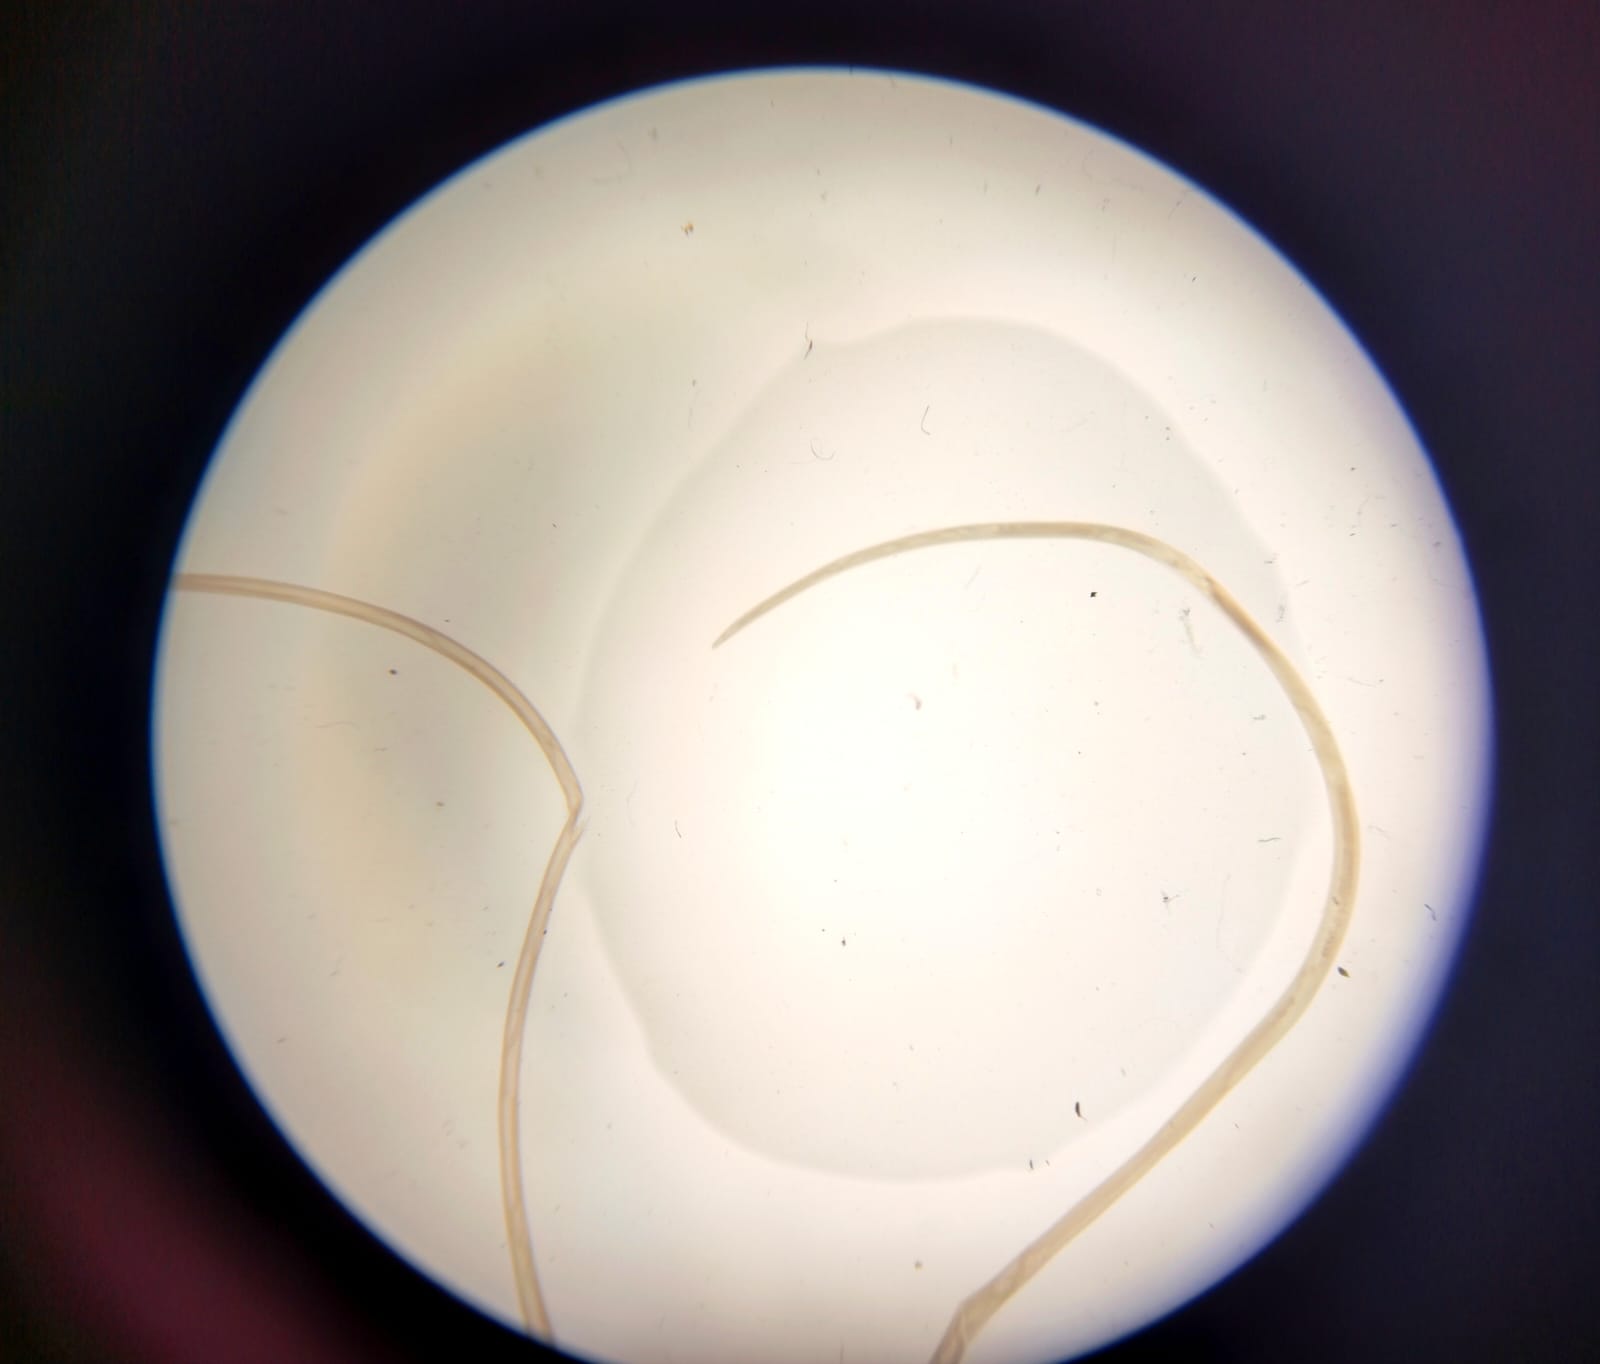

Захворювання на дирофіляріоз серед мешканців м. Запоріжжя виявляється спорадично: 2023 рік – 3 випадки; 2024 рік – 5 випадків; перше півріччя 2025 року – 1  випадок. 8 із 9 пацієнтів не виїжджали за межі Запорізької області останні 2 роки перед захворюванням. Було госпіталізовано та прооперовано в стаціонарі – 2, амбулаторно -7. Гельмінти були видалені: з області голови – 6, в тому числі ока – 3; область тулуба – 3. Діагноз «дирофіляріоз» до оперативного втручання було встановлено у 6 хворих. Всі видалені гельмінти були доставлені на ідентифікацію до паразитологічної лабораторії Запорізький обласний центр контролю та профілактики хвороб. Останній випадок з локалізації хвороби на повікі ока був викликаний підшкірною дирофілярією і характеризувався міграцією гільмінта із області перенісся.

На фото під мікроскопом гельмінти Dirofilaria